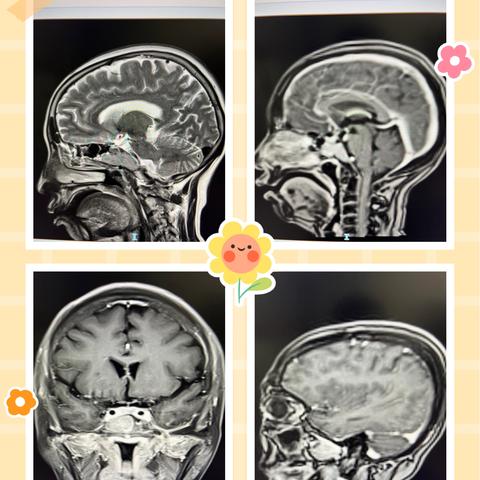

易被误认为脑转移瘤的病灶-多发胶质母细胞瘤